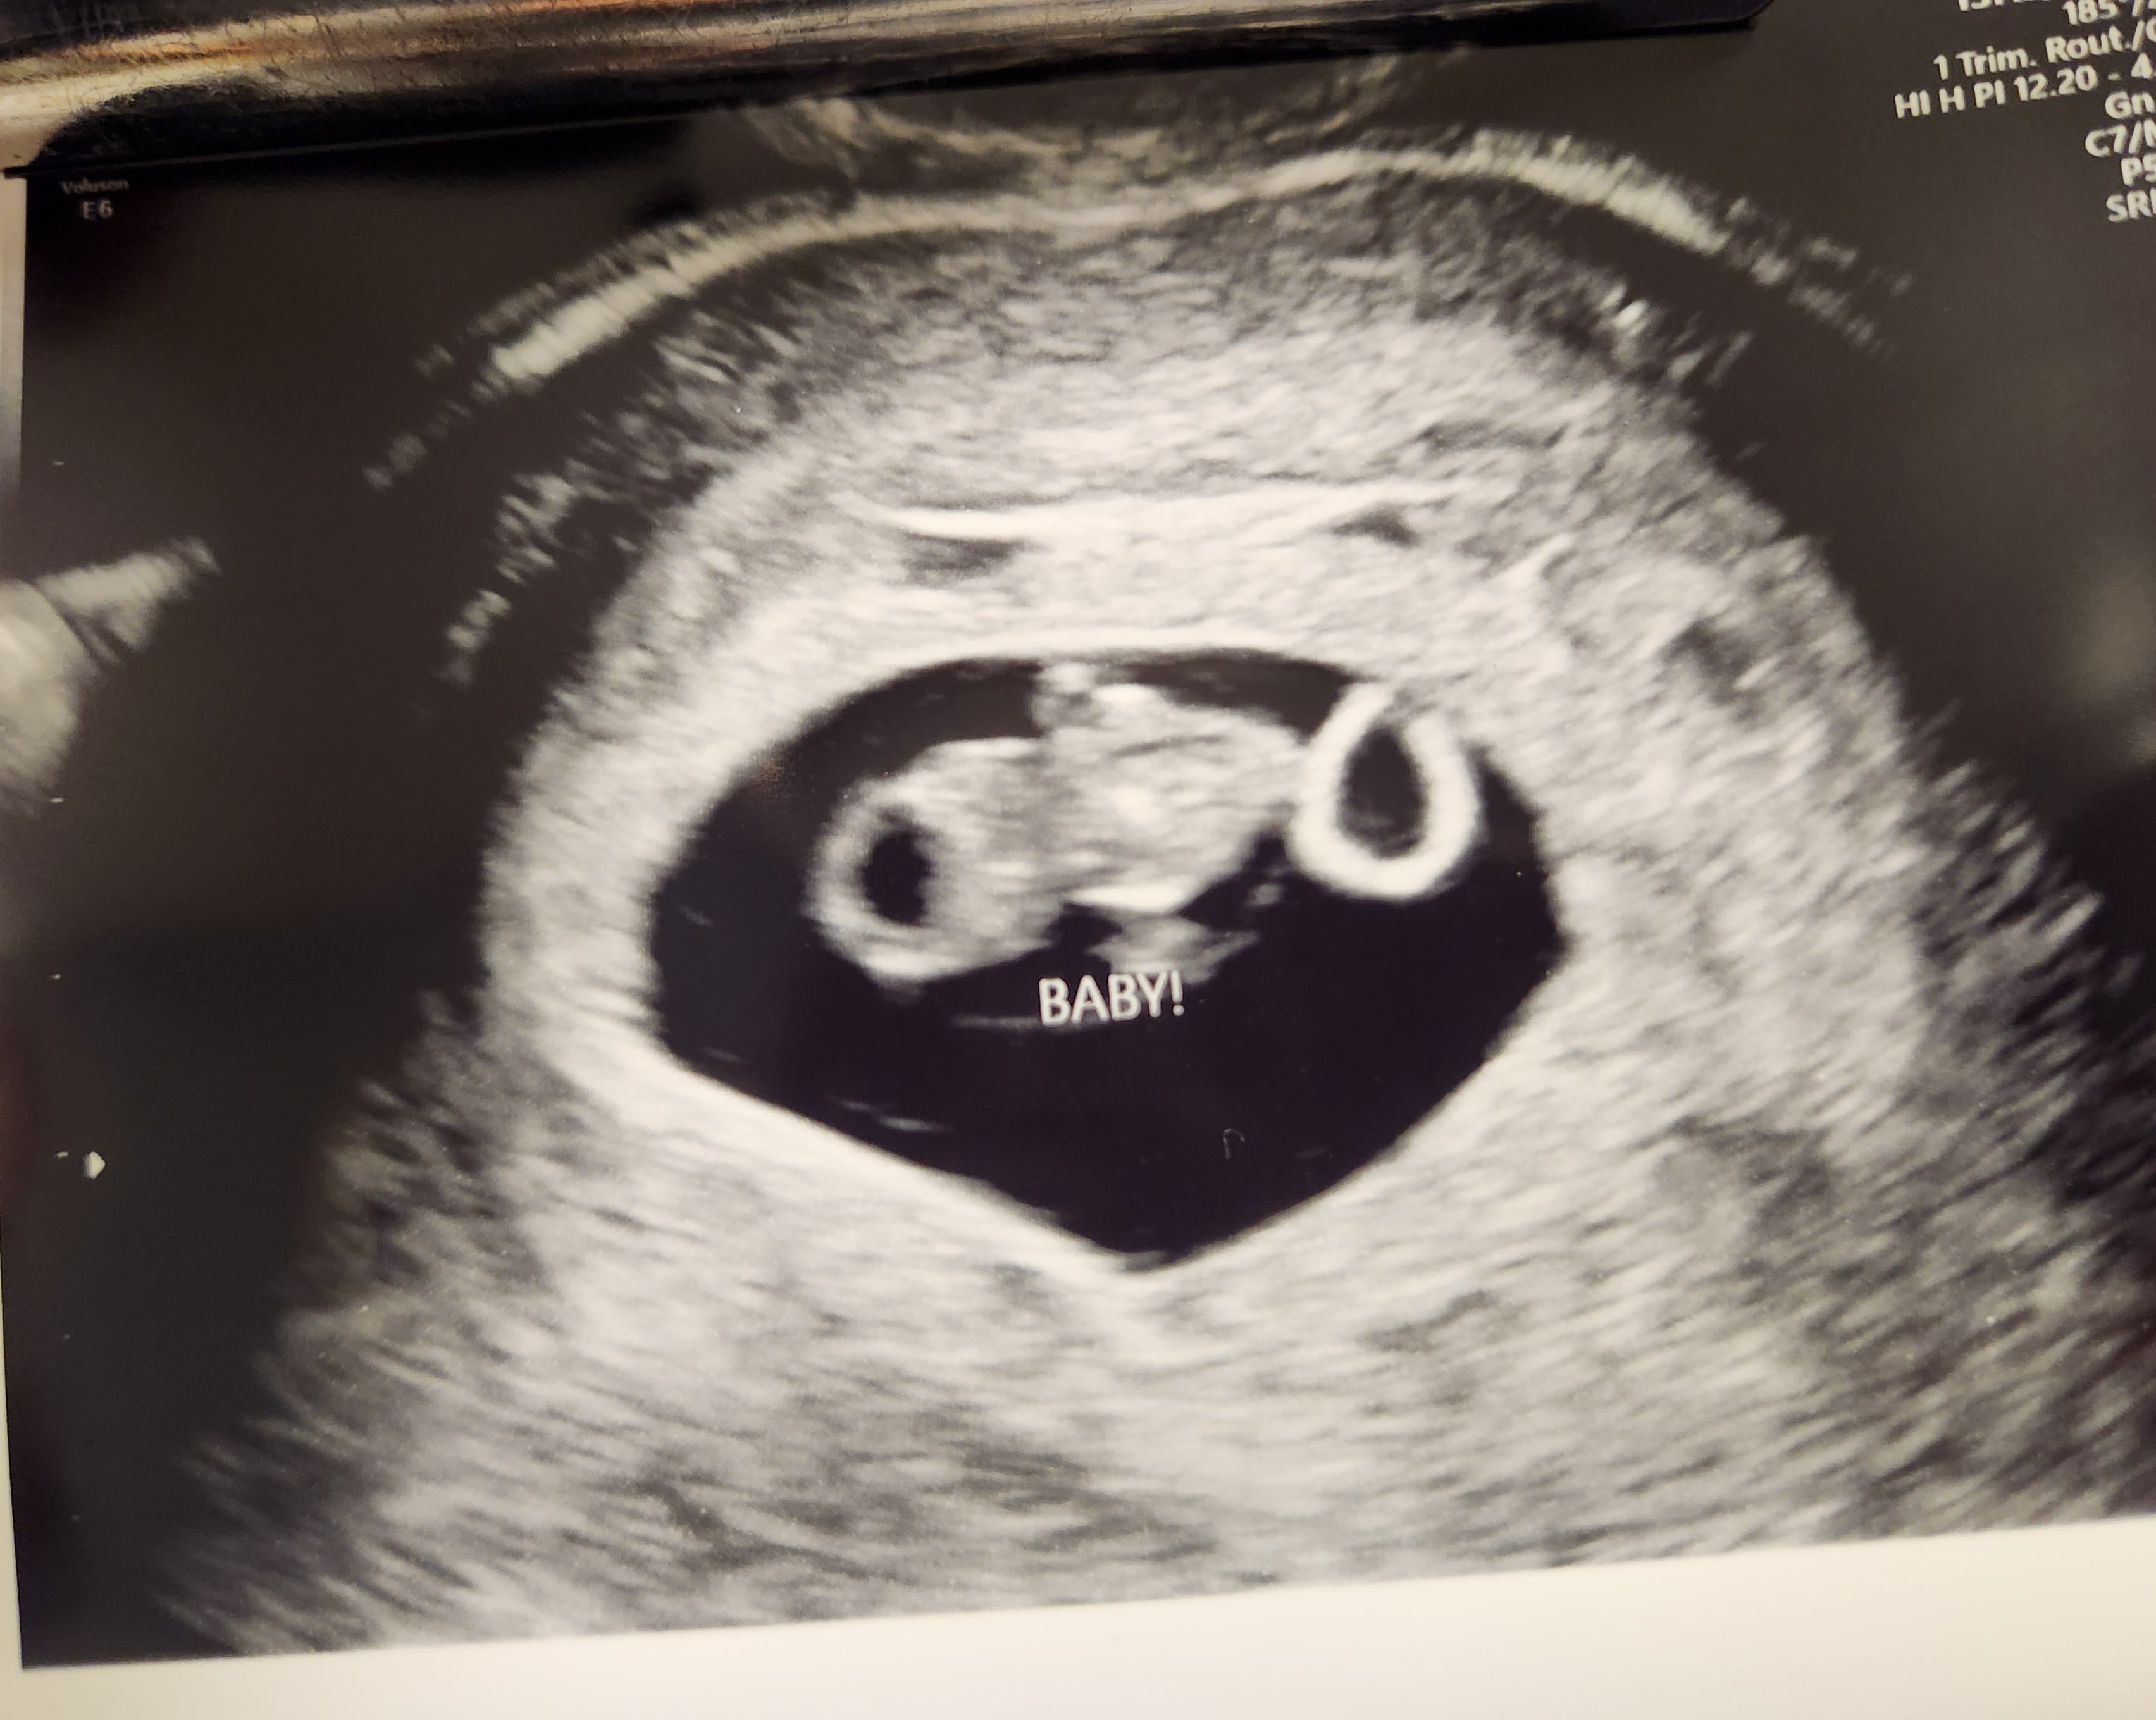

My wife and I have been married for over a year and we really wanted to start a family. We found a trusted donor and ordered the Mosie Baby Kit. After just 2 tries, I found out I was pregnant! We are so excited! We want to have a big family and plan to continue to use Mosie to help us!

- N&E from PA